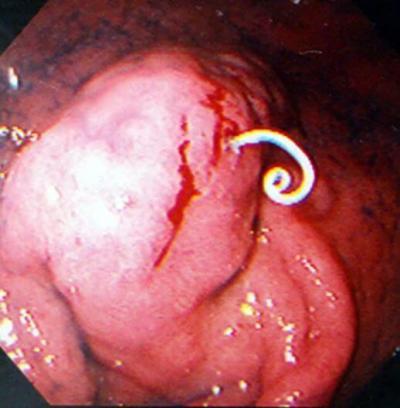

(庄司智春さんは)夜中に痛みで目覚めた。ロケから2日目、病院で内視鏡を使って約10時間かけて計8匹のアニサキスを取り除いた。胃の中はアニサキスに傷つけられて血だらけだったという。

新鮮な生鮭に寄生するアニサキスの画像がこちら

庄司智春さんの胃は8匹ものアニサキスに噛まれて、いたる所が血だらけ、さらに炎症を起こしていたといいます。美味しい「鮭いくら丼」の食リポの後に、自ら胃を食い散らかされる状況を経験したそうです!!